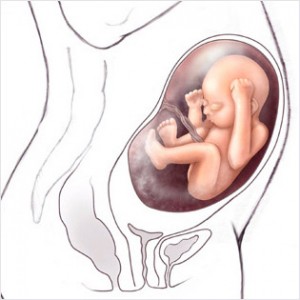

Hamileliğin (Gebeliğin) 35. Haftası Resim ve Video;

Bebeğin Boyutu: 43.7 cm, 1.9 kg

Çocuğun gelişimi: akciğerler alveollerin genişlenmesini sağlayacak ve doğduktan sonra bebeğinizin nefes alması için önemli olan surfaktan (Surfaktan maddeler en basit tanımı ile bir sıvının yüzey gerilimini azaltan maddelerdir) üretiyor.

Böbrekler tamamen gelişmiştir.

Bu haftadan itibaren artık bebek rahim içerisinde oldukça fazla yer kaplar ve bu yüzden ona hareket edecek fazla alan kalmaz. Eğer bebeğinizin hareketlerinde azalma his ederseniz endişe etmeyin, hareketlerin azalması bu yüzdendir.